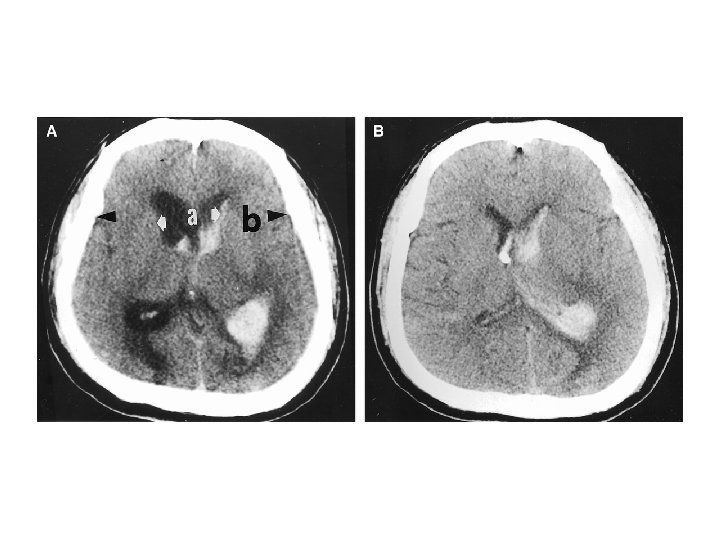

陰性 ↓ 1. Blood cultures (x 3), 2. Ischemic stroke evaluation, 3. Coagulopathy evaluation, 4. MRI c/s gadolinium, 5. Consider cerebral angiography • 血管攝影是一種侵襲性的檢查。 • 血腫的大小是評估預後最好的 具。 • Volume: estimated from CT ( A x B x C) / 2 A = the greatest diameter of hematoma B = the diameter perpendicular to A C = the thickness measured as the number of CT slices where the hematoma is visualized multiplied by slice thickness.

• Hematoma enlargement or hematoma growth - increase in the volume of hematoma, can occur several hours after stroke onset, frequently associated with neurologic deterioration (66%). * initial CT scan < 3 hrs (35%) * at 3 – 6 hrs (16%) * at 6 – 12 hrs (15%) * at 12 – 24 hrs (6%) - Predisposing factors: history of brain infarction; liver disease; high blood glucose ( >141 mg/dl) or Hb. A 1 C ( >5. 1%); high systolic

blood pressure ( > 200 mm Hg). - Predictors: short time interval between onset and admission; habitual alcohol consumption; consciousness disturbance; an irregularly shaped hematoma shown on initial CT scan; and low levels of fibrinogen. • Outcome - mortality rate from ICH decreased dramatically due to: * increased detection rate of milder ICH. * decrease in the prevalence of HTN. * improved antihypertensive therapy.